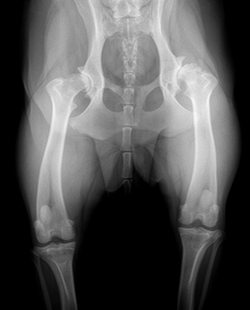

Diagnosis of osteoarthritis in dogs and cats is generally straightforward and performed by either taking radiographs (X-rays) or observing cartilage changes in the joint during surgery. X-rays are also a good tool to monitor for progression of arthritis and we recommend performing these annually of each joint affected if possible.